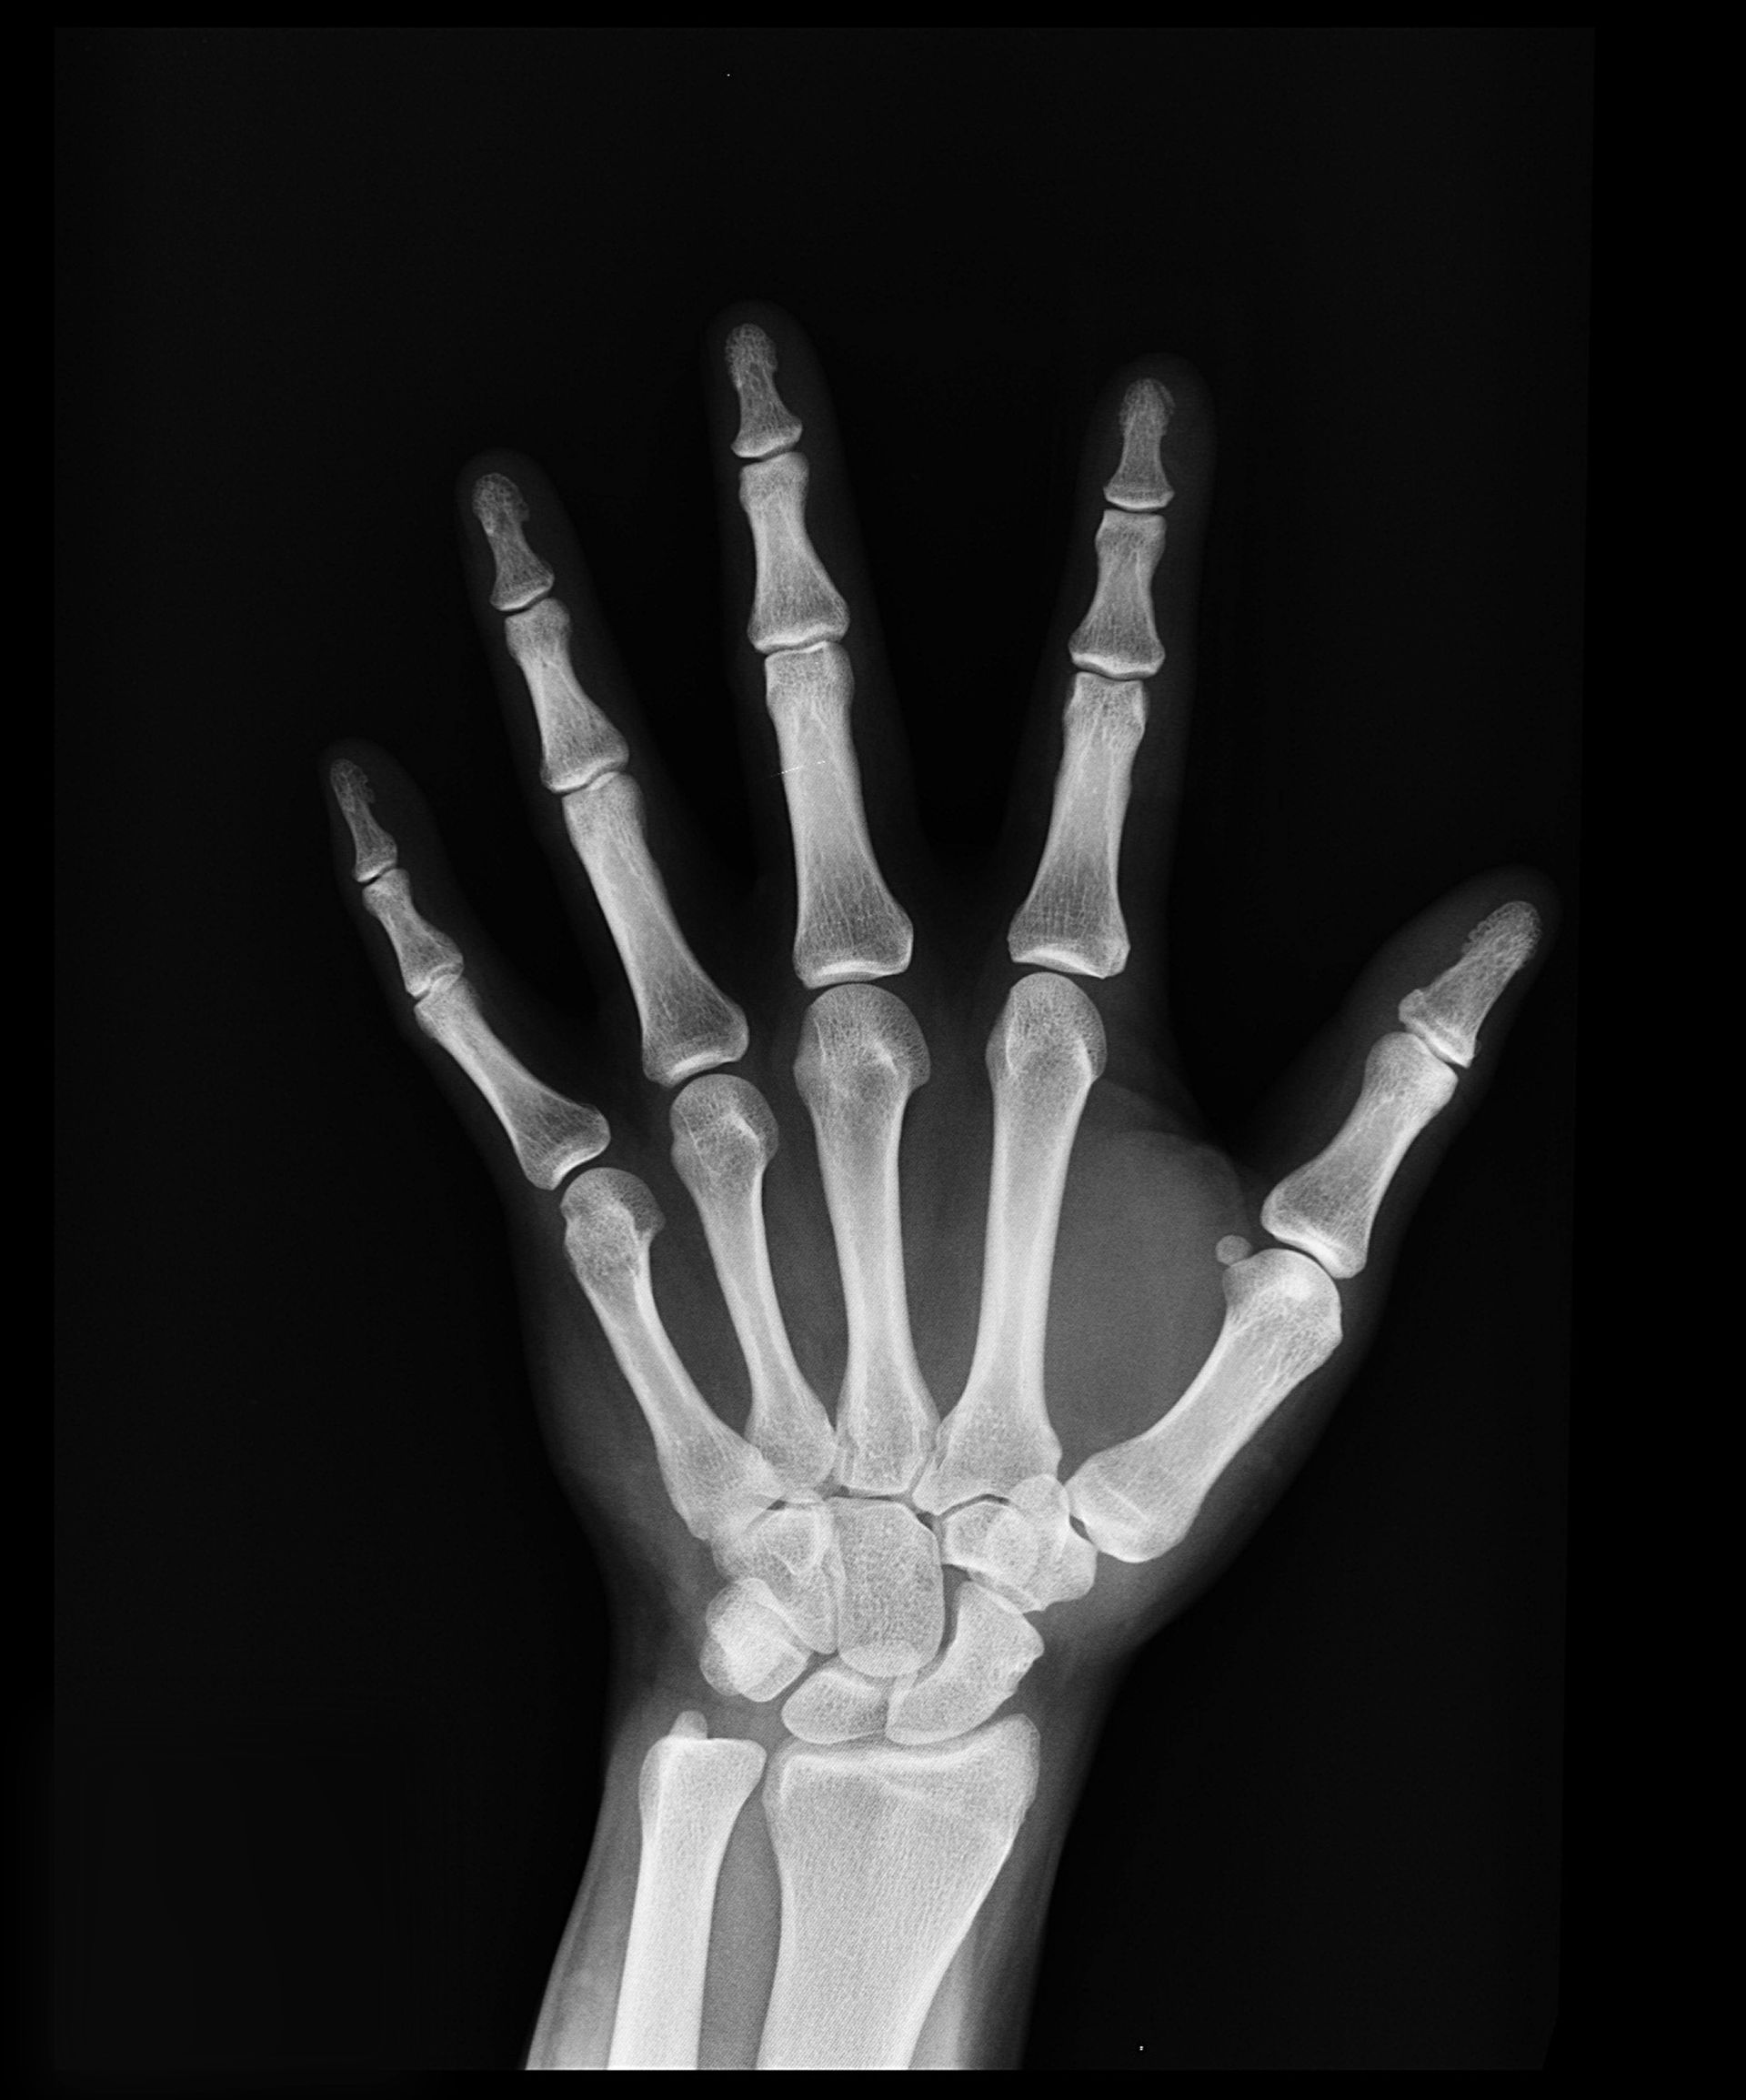

The pain experienced with Carpal Tunnel Syndrome is a result of the swelling and misalignment of tissues and bone which then press on the nerve. Often there is an underlying problem. Some patients have had an obvious injury, a stress or break to the wrist, that causes the symptoms to develop.

The most common cause is related to occupations that involve the long term use of vibrating instruments and the repetitive use of the hands and wrist. At other times, this issue seems to develop out of nowhere. Metabolic disorders involving the pituitary and thyroid gland can be a contributing factor to the unexplained development of Carpal Tunnel Syndrome, as can pregnancy and obesity. More commonly, Carpal Tunnel Syndrome, that develops in one or both wrists without a clear cause, is the result of a nerve irritation stemming from the spine.